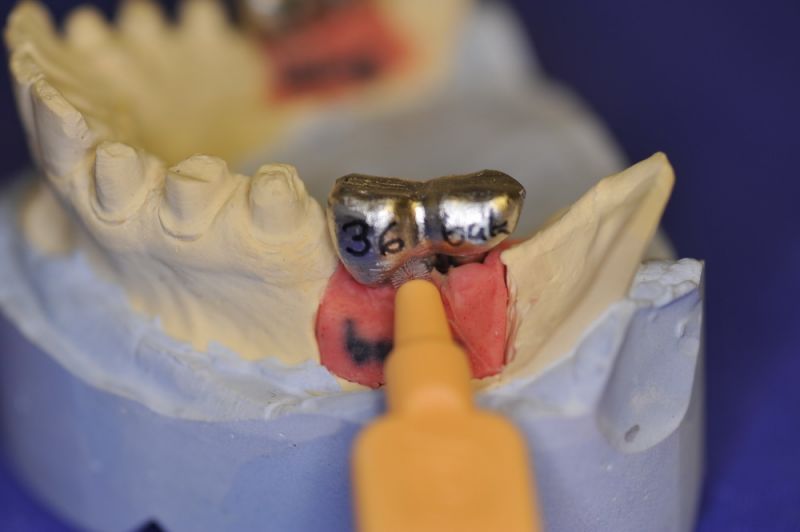

Mit dem heutigen Tag geht eine der technisch schwierigsten und anspruchsvollsten Arbeiten zu Ende, die im CMD-CENTRUM-KIEL jemals erstellt worden ist. Dabei sind es nur 10 Kronen, die benötigt werden, um die starken Kopf- und Gesichtsschmerzen der Patienten zu beseitigen.

3. Sehr dünne Implantate, die von ursprünglich zwei je Kieferhälfte auf letztendlich drei je Kieferhälfte umgeplant werden mussten.

4. Notwendigkeit die Mundhygienefähigkeit der Arbeit auch unter sehr beengten Verhältnissen zu schaffen, um der Arbeit eine günstige Prognose mitzugeben.